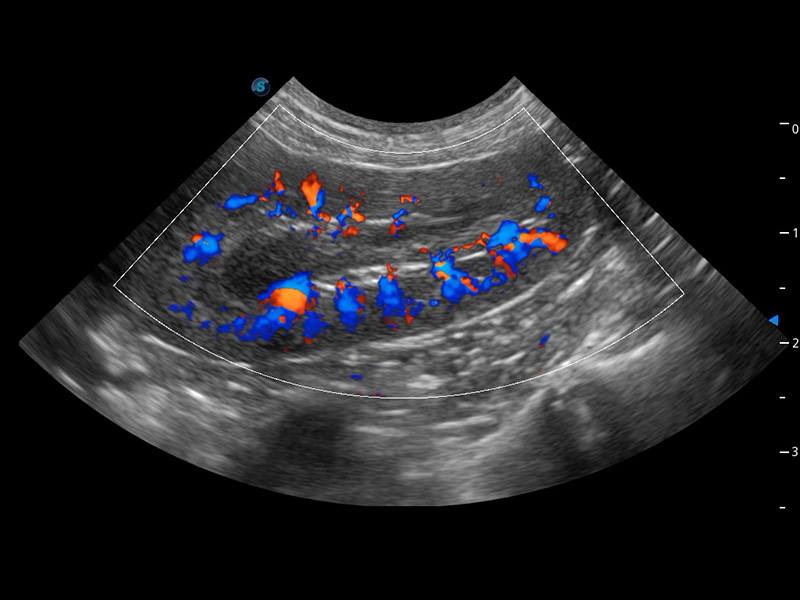

优异的基础图像

(犬)肾脏血流